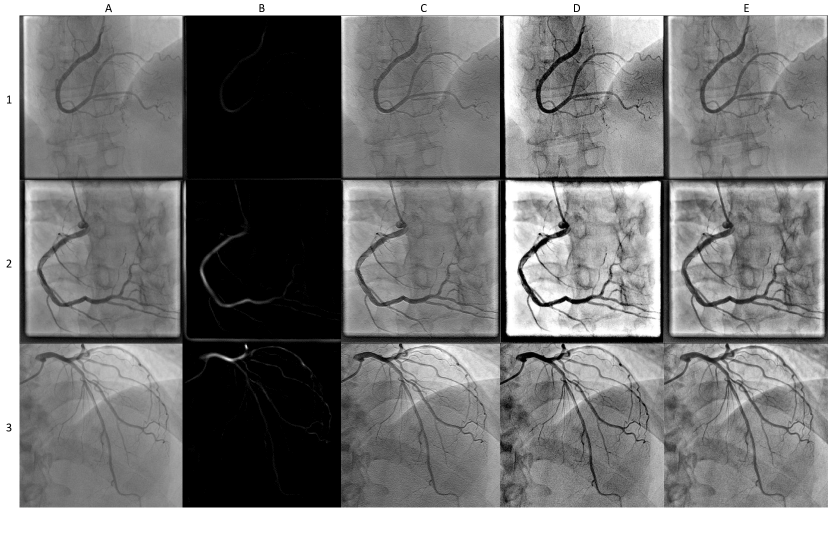

Refer to caption

Figure 1: Gives an overview of various preprocessing methods in cornary angiography. A1-A3. Shows raw images; B1-B3. Shows the result of application of Hessian-based Frangi Vesselness filter; C1-C3. Shows images after the top-bottom hat transform was applied; D1-D3. Shows the result of applying MSRCR; E1-E3. Shows the results of CLAHE on test images.

The first example is the top-bottom hat transform, as can be seen in the third column of Fig. 1C. The top-bottom hat transform is one of the most common and computationally simple tools for edge visibility enhancement. It is based on multiscale high- and low-pass filters. High-pass filters leave only the bright spots, which usually represent vessels on the image, while low-pass filters aim to leave only the background of the image. The resulting filtered image is obtained by the following formula [44]:

Contrast Limited Adaptive Histogram Equalization (CLAHE) is an image preprocessing algorithm [47], for improved visibility of lesions on mammogram images. This method is based on the application of Adaptive Histogram Equalization (AHE) on small regions of the image, called tiles, instead of the whole image. Individual tiles are then combined using interpolation techniques, in order to remove artificial boundaries, occurring after equalization. Currently, this method is widely applied in retinal image segmentation [48], chest x-ray images [49], and also found in the application of XCA segmentation [50] An example of CLAHE on coronary angiograms can be found in the fifth column of Fig. 1E.

Multi-scale Retinex with Color Restoration (MSRCR) is an algorithm designed to remove the artifacts from the image while preserving sharpness on the edges by providing color constancy and dynamic color range suppression [46]. It is a computationally efficient tool and results in the improvement of the image structure, effectively removing noise from the angiogram. It is often considered as an important step in the preparation of images for further preprocessing methodologies such as [51], since this methodology is known to be highly sensitive to small artifacts left by noise. Further development of classic MSRCR architecture was proposed in [52]. Zhang and colleagues had utilized MSRCR in a pipeline, consisting of Singular Value Decomposition in the RGB color space, automated MSRCR and Gamma Stretching for luminance and saturation enhancement in the HSV color space, and Guided Filtering for final denoising in RGB space. Examples of application of classical MSRCR on XCA images can be found in [53] and on Fig. 1D.

While having been discovered several decades ago, Hessian filters are still commonly employed with new modifications being released up to this date [54]. In fact, they remain one of the most useful and popular baseline methods for unsupervised image enhancement and segmentation to this day [55, 56, 57, 58]. Practical applications of Hessian filters for tubular structures detection can be observed on the Fig. 1B.